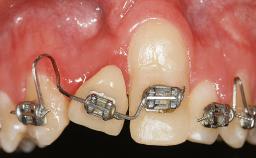

This case demonstrates that a connective-tissue graft in combination with a coronally positioned graft is an effective method of treating cases with peri-implant mucositis and an abutment-level sinus abscess. A 42-year-old man presented with a swelling adjacent to an implant crown at site 21. The swelling had been present for approximately three weeks and was constrained to the buccal and palatal gingival aspects of the implant. A discharge was noted on finger pressure, with localized gingival recession present on the mid- and distolabial aspects of the crown.